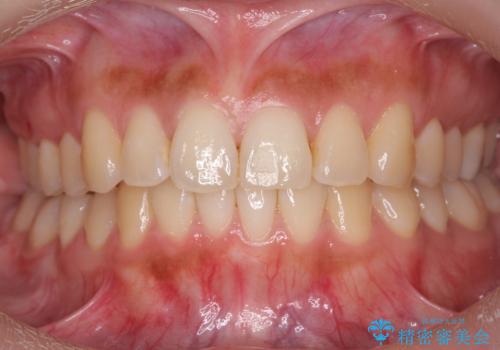

- 前歯のがたつきを主訴に来院。

前歯は目立つのでワイヤー矯正は絶対にしたくないとのことでした。

右上の奥歯を後ろに送り、前歯が出っ歯にならないように並べました。

また、右下の奥歯に一部目立たないように部分的なワイヤー矯正を行い、右下の奥歯が反対咬合になっていたのもしっかり中に入れて治療しています。

奥歯の反対咬合を治すのはインビザラインではかなり難しいのですが、しっかり治療できました。